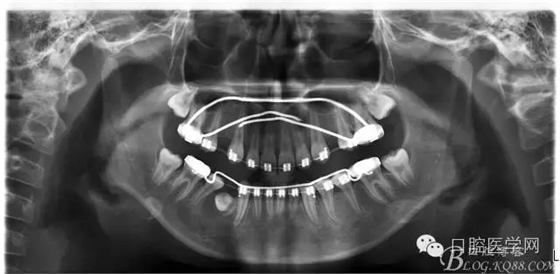

3:上下頜利用拔牙間隙解除擁擠并內(nèi)收上下前牙,改善唇側(cè)貌。

4:導(dǎo)下頜向前改善頜面?zhèn)让病?p style="text-indent: 2em; text-align: left;">5:上頜TPA+NanceArch強(qiáng)支抗.

6:下頜囊腫開窗引流,雙側(cè)第一恒磨牙舌桿保持牙位。擇期拔除第一前磨牙。

正畸后照片: